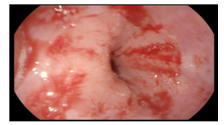

2021.02.24:外院胃镜活检组织病理切片提示胃角低分化腺癌,lauren分型:弥漫型。

图2 胃镜活检组织病理切片